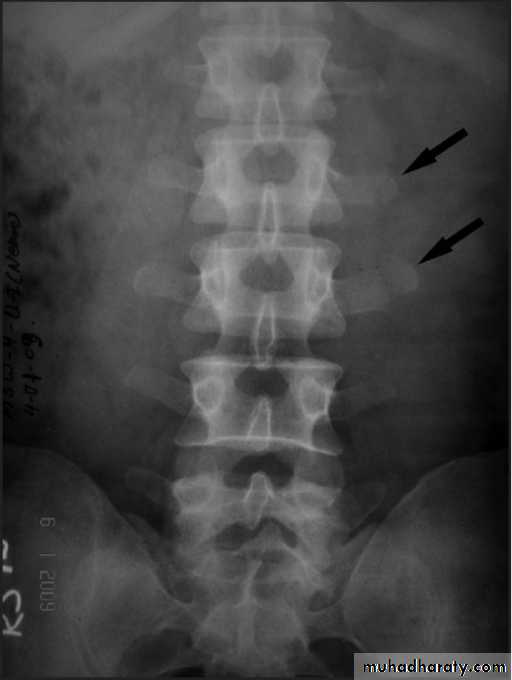

Dorsal and lumbar spine

Wedge compression fracture of a vertebral body.

WEDGE COMPRESSION FRACTURE

Diagnosis .

In cases of major fracture there will be only between the T11 and L2